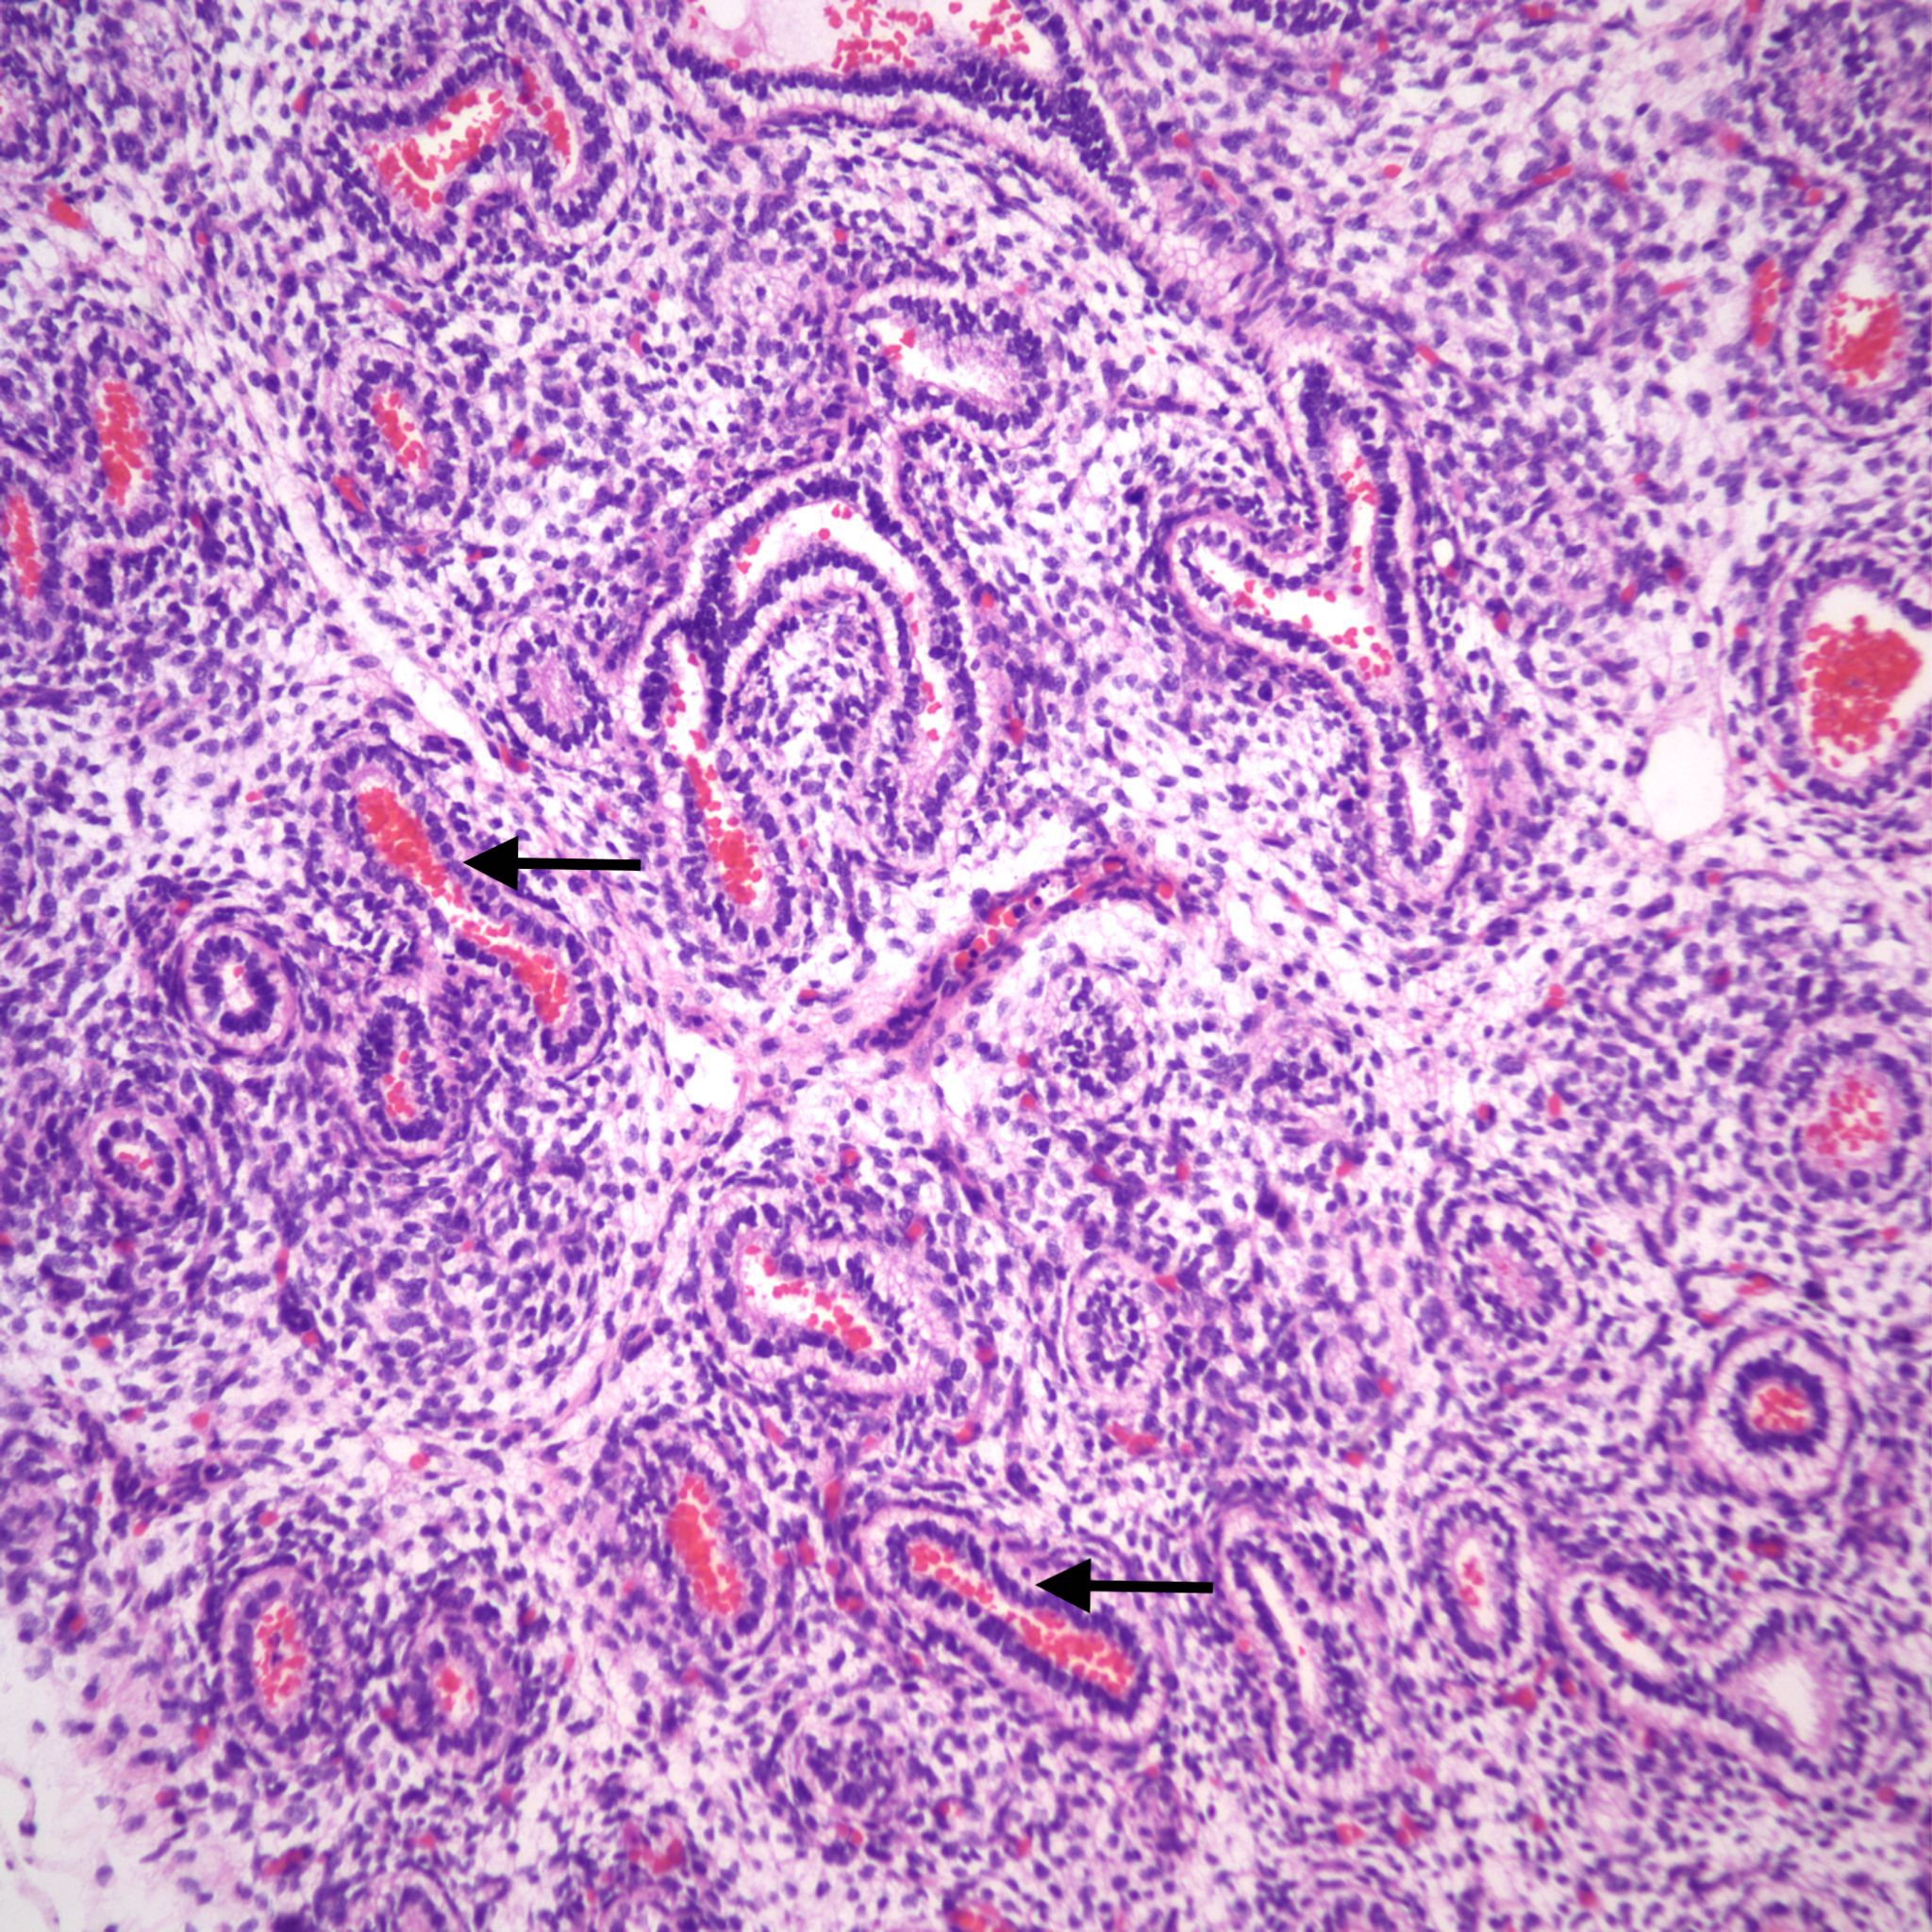

Infection: Even without gasping, microorganisms and neutrophils present in infected amniotic fluid would be able to traverse into the airways from normal, shallow respiration. This is also likely true for mobile neutrophils in the amniotic fluid. In previable fetuses, cuboidal cells lining the airways shed into the lumen and undergo karyorrhexis (apoptosis) that may resemble, but are morphologically distinct from neutrophils (fig 11a,b).

However, the karyorhectic cells lack the intact cytoplasm of neutrophils. It is not possible to observationally determine whether neutrophils in the airway are from aspiration of neutrophils in the amniotic fluid, or are from fetal neutrophils in response to aspirated bacteria. The exception is with focal bronchopneumonia which demonstrates a fetal inflammatory response with large, focal accumulations of neutrophils and vasodilatation of surrounding capillaries (fig 12a,b).